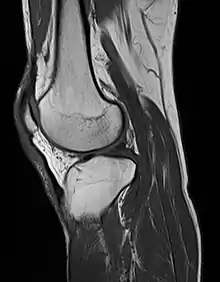

الرنين المغناطيسي

مقالة مفصلة: الرنين المغناطيسي

يستخدم التصوير بالرنين المغناطيسي حقول مغناطيسية قوية لمحاذاة النوى الذرية (عادة بروتونات الهيدروجين) داخل أنسجة الجسم ، ثم يستخدم إشارة لاسلكية لتعكير محور دوران هذه النوى ويلاحظ إشارة التردد الراديوي الناتجة عن عودة النواة إلى حالات خط الأساس. يتم جمع الإشارات الراديوية بواسطة هوائيات صغيرة تدعى لفائف ، موضوعة بالقرب من منطقة الاهتمام. ميزة التصوير بالرنين المغناطيسي هي قدرتها على إنتاج الصور في المحوري ، والإكليلية ، السهمي ، والعديد من الطائرات المائلة بسهولة متساوية. التصوير بالرنين المغناطيسي يعطي أفضل تباين للأنسجة اللينة بين جميع طرائق التصوير. مع التقدم في سرعة المسح والفضاء المكاني، والتحسينات في خوارزميات الحاسب ثلاثية الأبعاد والأجهزة، أصبح التصوير بالرنين المغناطيسي أداة مهمة في الأشعة الشعاعية والعضلية.

يوجد عيب واحد هو أن المريض يجب أن يبقى صامداً لفترات طويلة من الوقت في مكان ضيق وصاخب أثناء إجراء التصوير. تم الإبلاغ عن الخوف من الأماكن المغلقة (الخوف من الأماكن المغلقة) القاسية بما يكفي لإنهاء فحص التصوير بالرنين المغناطيسي في ما يصل إلى 5 ٪ من المرضى. وقد أدت التحسينات الأخيرة في تصميم المغناطيس بما في ذلك المجالات المغناطيسية الأقوى (3 teslas)، وتقصير أوقات الاختبار، وأقواس المغنط الأقصر والأقصر وتصاميم مغناطيسية أكثر انفتاحًا، إلى توفير بعض الراحة للمرضى الذين يعانون من الخوف من الأماكن المغلقة. ومع ذلك، بالنسبة إلى المغناطيسات ذات شدة المجال المكافئة، غالباً ما يكون هناك مفاضلة بين جودة الصورة والتصميم المفتوح. التصوير بالرنين المغناطيسي له فائدة كبيرة في تصوير الدماغ والعمود الفقري والجهاز العضلي الهيكلي. لا يتم حاليًا استخدام التصوير بالرنين المغناطيسي للمرضى الذين يعانون من أجهزة تنظيم ضربات القلب، وزرع القوقعة الصناعية، وبعض مضخات الدواء الساكن ، وأنواع معينة من تمدد الأوعية الدموية الدماغية ، وشظايا معدنية في العين وبعض الأجهزة المعدنية بسبب الحقول المغناطيسية القوية والإشارات الراديوية القوية المتقلبة التي الجسم مكشوف. وتشمل مجالات التقدم المحتمل التصوير الوظيفي، التصوير بالرنين المغناطيسي القلب والأوعية الدموية، والعلاج بالرنين المغناطيسي.